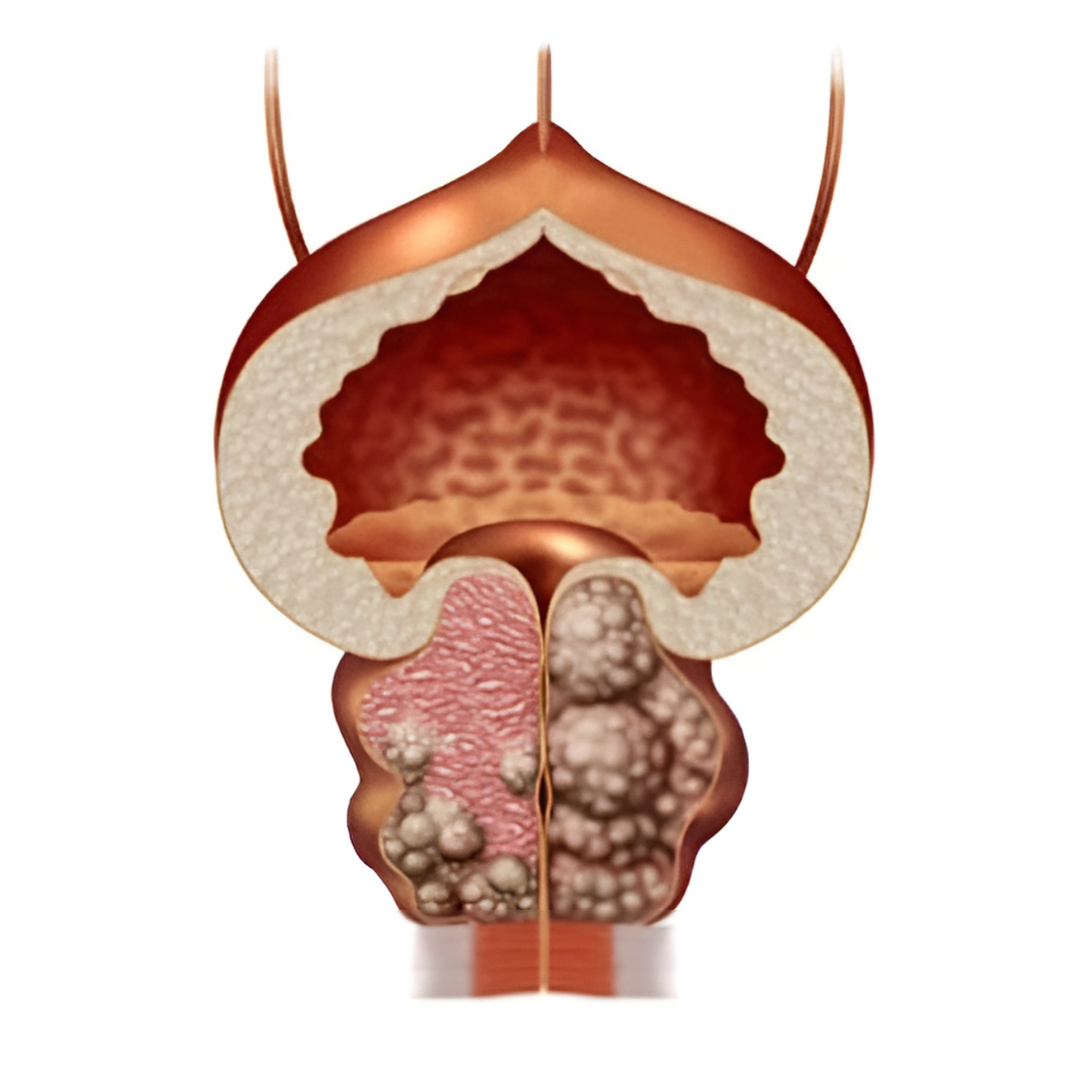

Възпалена простата - (Простатит)

Увеличена простата - (Хиперплазия) - Затруднено уриниране

Парене при уриниране - (Цистит)

Възпалената простата не е шега...

👉 и не бива да се подценява понеже нелекуването:

Води до загуба на ерекция и дисфункция...

Поради затрудненото уриниране се увреждат и бъбреците...

Дългото нелекуване може да доведе и до камъни в пикочния мехур...